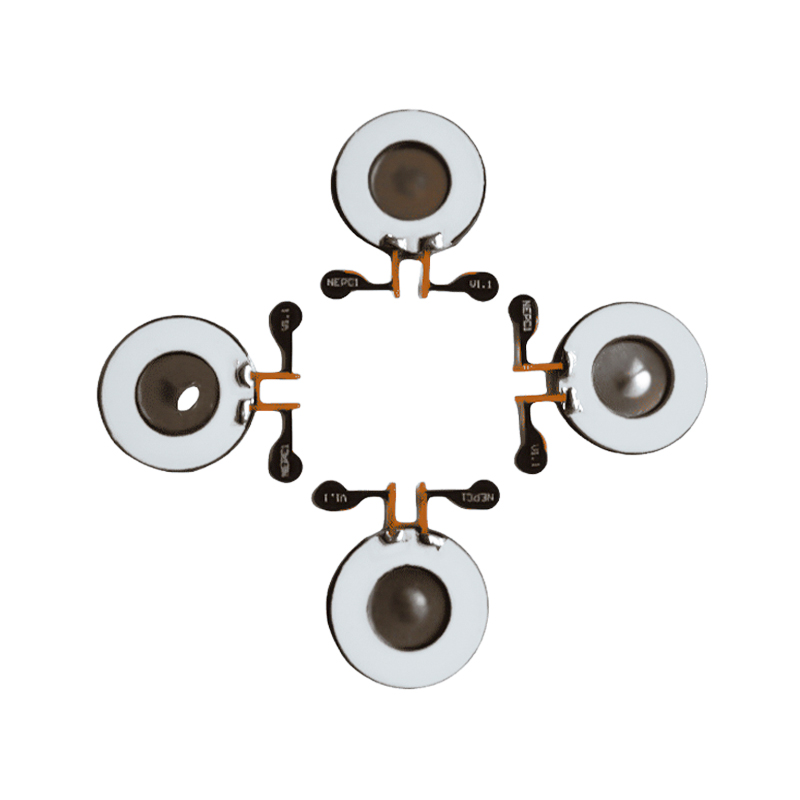

Medyczne tabletki do nebulizatora siatkowego to precyzyjne elementy stosowane w urządzeniach medycznych do przekształcania leków lub roztworów w drobne cząsteczki aerozolu w celu leczenia różnych chorób układu oddechowego, takich jak astma i przewlekła obturacyjna choroba płuc (POChP) itp., poprzez inhalację. Konstrukcja i dobór materiału arkusza nebulizatora mają kluczowe znaczenie dla zapewnienia skutecznego podawania leku i komfortu pacjenta. Arkusz membrany ze stali nierdzewnej jest dziurkowany w blasze stalowej tysiącami drobnych otworów o oczkach 2-3 μm za pomocą technologii wiercenia laserowego w precyzyjnym procesie laserowym, a następnie jest ściśle połączony z okrągłym arkuszem ceramicznym piezoelektrycznym, który przekształca częstotliwość rezonansową arkusza piezoelektrycznego w energię wibracji o wysokiej częstotliwości poprzez sygnał wyjściowy płytki sterownika PCB i szybko rozkłada płynny lek na drobne cząsteczki aerozolu. Krople te nazywane są również medianą wielkości cząstek. Gdy mediana wielkości cząstek D50 osiąga >60% lub więcej, cząstki będą wystarczająco małe, aby podczas oddychania móc dotrzeć głęboko do płuc do powierzchni pęcherzyków płucnych, poprawiając w ten sposób skuteczność wchłaniania leku i efekt terapeutyczny. Arkusz nebulizatora z mikrosiatką medyczną ma głównie kilka form, arkusz nebulizatora z mikrosiatką ze stali nierdzewnej, arkusz nebulizatora medycznego z niklowo-palladem, arkusz nebulizatora medycznego z polimeru PI i tak dalej. Wszystko powyższe odbywa się poprzez piezoelektryczną konwersję energii wibracji ceramicznych w celu osiągnięcia efektu atomizacji.

Poliimid (poliimid) określany jako PI to najlepsze kompleksowe działanie organicznych materiałów polimerowych, ma doskonałą stabilność chemiczną i może wytrzymać korozję różnych leków, aby zapewnić długotrwałe użytkowanie rozpylonych tabletek. Ponadto stabilność termiczna folii polimerowej PI jest również doskonała, przy długotrwałym stosowaniu w zakresie temperatur -200 ~ 300 ° C, wysokiej izolacji, ochronie środowiska i nietoksyczności, jako specjalny materiał inżynieryjny, szeroko stosowany w mikroelektronice lotniczej, membranach do separacji nano-ciekłych kryształów i innych dziedzinach, został włączony w XXI wieku przez kraje do jednego z najbardziej obiecujących materiałów inżynieryjnych i nie jest łatwo go osiągnąć zdeformowany w procesie dezynfekcji wysokotemperaturowej, aby mieć pewność, że produkt zostanie ponownie użyty! Ze względów seksualnych i bezpieczeństwa używamy technologii laserowej do perforacji laserowej, folii PI wszczepianej pomiędzy stal nierdzewną a arkusz piezoelektryczny, stosowania piezoelektrycznej ceramicznej technologii ultradźwiękowej, dzięki czemu rozpylone kropelki przez folię PI rozpraszają się w atomizacji cząstek o wielkości 3 ~ 4 μm do inhalacji nebulizacyjnej medycznej, bezpieczeństwo uwielbiane przez większość użytkowników, wykonane z nebulizatora z Główną zaletą PI jest brak zatykania, wewnętrzna ściana otworu jest gładka i zaokrąglona, brak pozostałości cieczy, atomizacja drobna i stabilna. Atomizacja jest delikatna i stabilna. Tabletki do nebulizacji z folią PI mogą skutecznie zapobiegać pozostałościom leków, zmniejszać ryzyko zanieczyszczenia krzyżowego. W praktyce odzwierciedlono również niskie zużycie energii przez tabletki do nebulizacji z membraną polimerową PI, podsumowując, tabletki do nebulizacji z membraną polimerową PI dzięki swoim doskonałym właściwościom użytkowym i zaletom konstrukcyjnym stały się nieodzowną częścią dziedziny medycznej terapii nebulizacyjnej.

Bezołowiowa ceramika piezoelektryczna jest znana jako „perła” przemysłu piezoelektrycznego, w przyszłości stopniowo zastąpi ona we wszystkich aspektach ceramikę piezoelektryczną na bazie ołowiu, która ma już tę samą wydajność piezoelektryczną, oraz blachę piezoelektryczną na bazie ołowiu. Jest całkowicie nietoksyczny, nieszkodliwy, bezpieczny i przyjazny dla środowiska, nie zawiera ołowiu, antymonu i innych metali ciężkich oraz innych pierwiastków objętych ograniczeniami Rohs, wysoka temperatura Curie Tc-328°C, bardzo niska strata elektryczna TangentLoss Dlatego bezołowiowy piezoelektryczny chip do atomizacji medycznej ma wielką wartość handlową i wartość uniwersalną, naprawdę nietoksyczną i przyjazną dla środowiska, bezołowiową ceramikę piezoelektryczną, a także niezanieczyszczającą, piezoelektryczną wydajność porównywalną z ceramiką na bazie ołowiu, stanie się popularną przyjazną dla środowiska ceramiką piezoelektryczną. Po latach badań i rozwoju, po ciągłych testach i eksperymentach, firmie udało się wyprodukować bezołowiowy medyczny chip atomizujący, który pozwala uzyskać taką samą ilość atomizacji jak chip atomizujący na bazie ołowiu, a także wymagania dotyczące cząstek o tej samej średnicy. Bezołowiowy chip nebulizatora medycznego Mesh z pewnością zabłyśnie i znajdzie szerokie zastosowanie.

Płytki i przetworniki kosmetyczne ultradźwiękowe wykonane są z ceramiki piezoelektrycznej. Zasada ich działania opiera się na efekcie piezoelektrycznym, polegającym na generowaniu fal ultradźwiękowych poprzez przyłożenie napięcia, które powoduje wibrację materiału. Przetworniki ultradźwiękowe są projektowane z precyzją, a materiały są starannie dobierane, aby zapewnić, że będą w stanie emitować fale ultradźwiękowe o określonych częstotliwościach i natężeniu, aby sprostać potrzebom różnych zastosowań. Ponadto przetworniki ultradźwiękowe mają dobrą trwałość i niezawodność oraz mogą utrzymywać stabilną pracę przez długi okres czasu. Dzięki wysokiej czułości i stabilności może szybko reagować na sygnały akustyczne w różnych mediach. Wykonany jest z wysokiej jakości materiałów charakteryzujących się dobrą odpornością na ścieranie i korozję, co gwarantuje stabilną pracę przez długi czas. Ponadto płytka przetwornika ultradźwiękowego ma zwartą konstrukcję i jest łatwa w montażu i konserwacji. Może być szeroko stosowany w czyszczeniu ultradźwiękowym, zgrzewaniu ultradźwiękowym, ustawianiu odległości ultradźwiękowej itp., zapewniając wydajne i niezawodne rozwiązania w zakresie konwersji fal akustycznych do różnych zastosowań przemysłowych. Ceramika piezoelektryczna to materiały funkcjonalne, które mogą przekształcać w siebie energię mechaniczną i elektryczną. Poddane działaniu nacisku mechanicznego wytwarzają ładunek elektryczny, zjawisko znane jako dodatni efekt piezoelektryczny; i odwrotnie, gdy przyłożone zostanie pole elektryczne, odkształcają się, co jest zjawiskiem znanym jako odwrotny efekt piezoelektryczny. Ceramika piezoelektryczna jest szeroko stosowana w czujnikach, siłownikach, generatorach ultradźwiękowych, zbieraczach energii i innych dziedzinach. Na przykład czujniki mogą wykrywać niewielkie zmiany ciśnienia i przekształcać je na sygnały elektryczne; siłowniki mogą przekształcać sygnały elektryczne w precyzyjne ruchy mechaniczne. Ze względu na swoje unikalne właściwości fizyczne ceramika piezoelektryczna odgrywa ważną rolę w precyzyjnym sterowaniu i urządzeniach pomiarowych o wysokiej dokładności. Ultradźwiękowa ceramika piezoelektryczna ma wysoką czułość i stabilność oraz może skutecznie przekształcać energię elektryczną w energię akustyczną i kinetyczną, która jest szeroko stosowana w obrazowaniu medycznym, badaniach nieniszczących, pomiarze odległości i innych dziedzinach.